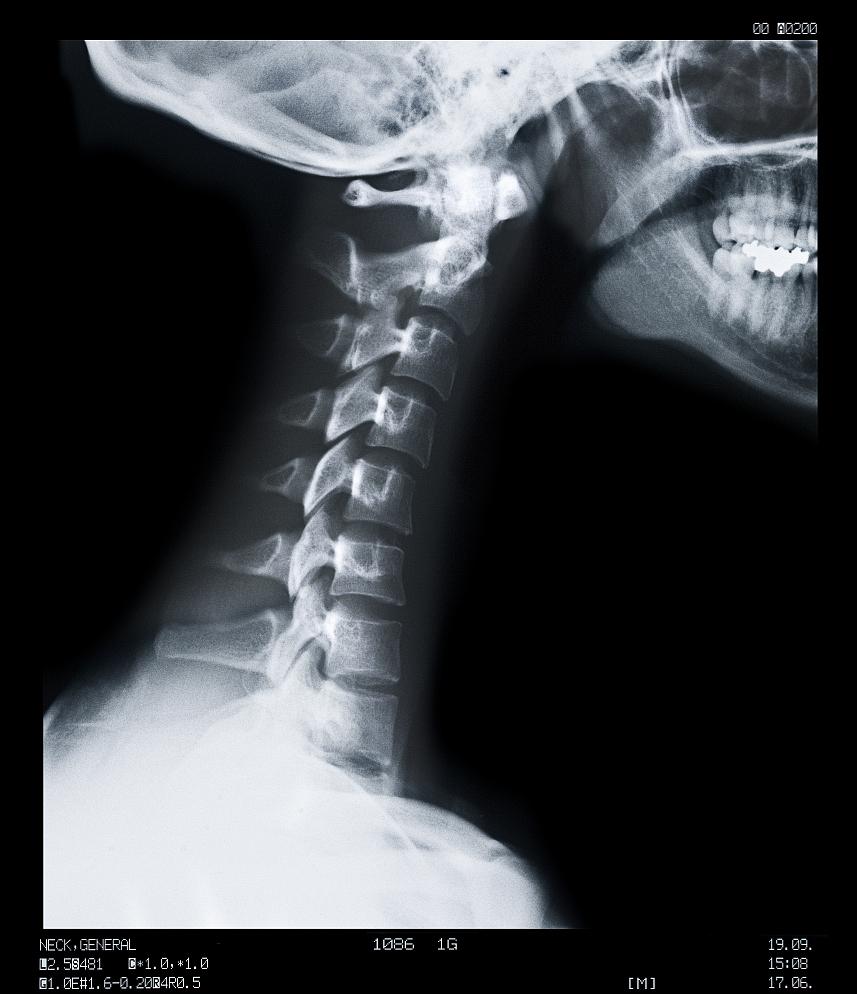

错误的颈椎排列 ▲

正确的颈椎排列 ▲

除了关注颈椎分拆的结构外,还要关注颈椎的生理曲度。

颈椎的生理曲度是指颈椎自然弧度的形态,具有一定的曲度是有利于颈部的生物力学特性和功能的。

通俗易懂地说,颈椎的生理曲度从侧面看就像一个反向“C形”的弧度,当头部自然地位于颈椎上方时,颈椎会呈现出一定的弯曲,形成前凸的形态。 这个生理曲度可以分为两个部分:颈椎的上曲和下曲。

颈椎的上曲是指颈椎C1和C2之间的弯曲,呈后凸状。颈椎的下曲是指颈椎C2到C7之间的弯曲,呈前凸状。

这种前凸的曲度使得颈椎能够承受重量和压力,保护脊髓和神经根,同时也有助于支撑头部并使颈部的运动更加自如和舒适。